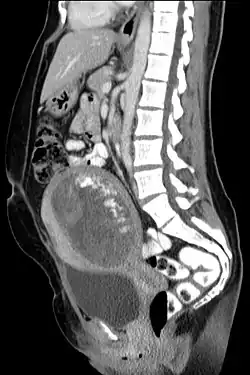

Die Blasenmole (Mola cystica) oder Traubenmole (Mola hydatidosa) ist eine Störung der Embryonalentwicklung in der Schwangerschaft. Durch eine Erweiterung der kleinen Plazentagefäße kommt es zu einer blasenartigen Umwandlung der Plazentazotten mit Einschmelzung des umgebenden Bindegewebes. Der Trophoblast zeigt eine gesteigerte Proliferationsaktivität.

Es wird zwischen teilweiser (90 %) und vollständiger (10 %) Blasenmole unterschieden. Die Übergänge zwischen der destruierenden (invasiven) Blasenmole und dem Chorionepitheliom sind fließend und in der Literatur nicht einheitlich. Begleitend zu einer Blasenmole treten bis kindskopfgroße Luteinzysten des Eierstocks auf, die sich infolge der hohen Sekretion von Gonadotropin (hCG) im Sinne eines Überstimulationssyndroms bilden.[1]

Anzeichen für eine Blasenmole können ein besonders schnell wachsender Uterus (Gebärmutter), ein hoch positiver Schwangerschaftstest, das Fehlen der fetalen Herztöne sowie besonders starke Schwangerschaftsübelkeit sein.

Die Diagnose wird über erhöhte Werte für das humane Choriongonadotropin (β-hCG) sowie über die Darstellung der verdickten Plazenta in Ultraschalluntersuchungen gestellt.